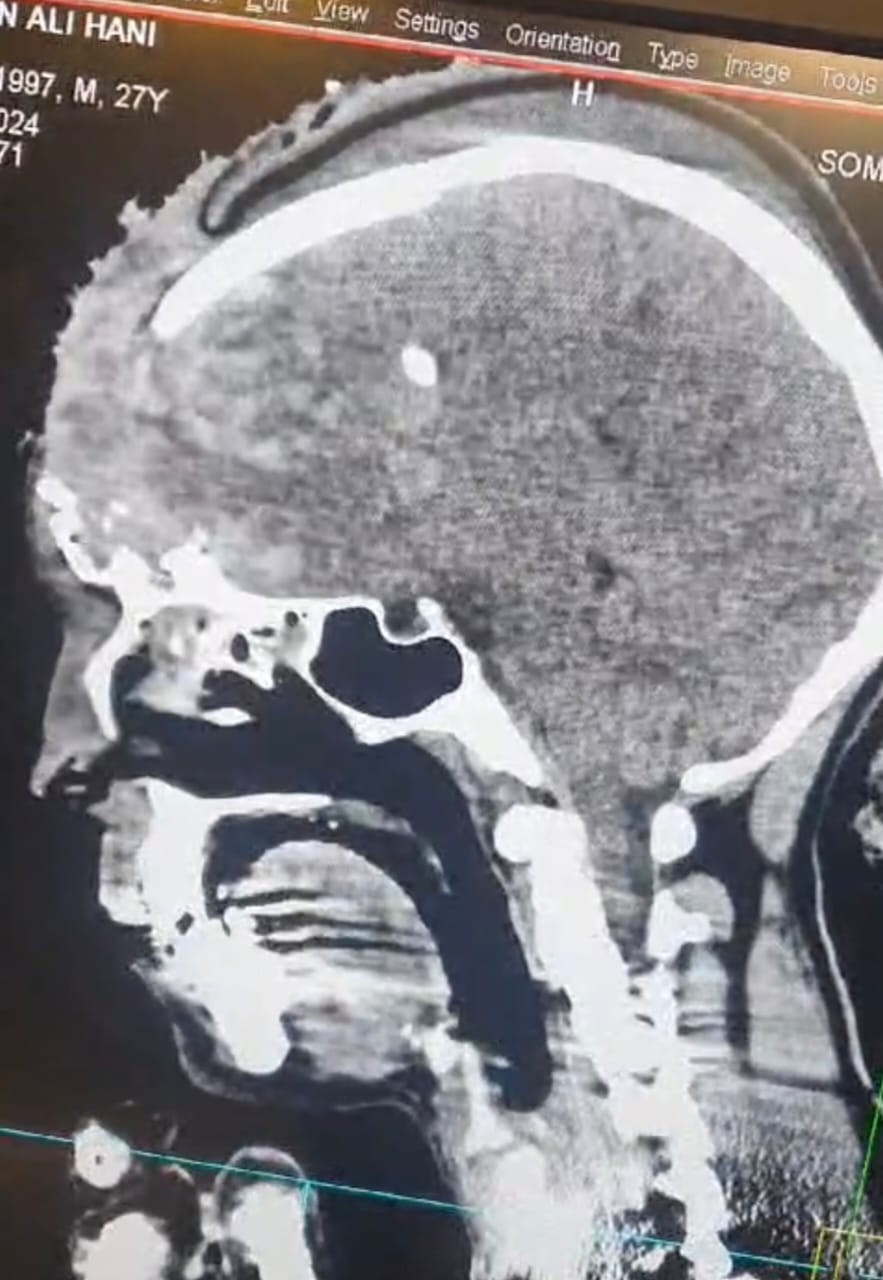

ذكر اخصائي جراحة الدماغ والعمود الفقري الدكتور مصطفى الحيدري بأن مريض شاب يبلغ من العمر (20) عام من أهالي السماوه تمت احالته من مستشفى الإمام الحسين في محافظة المثنى إلى مدينة الصدر الطبية في النجف كان قد تعرض لشدة خارجية على الرأس ادت إلى حدوث(نزف شديد و تهشم في عظم الجمجمه مع تمزق وتهتك الاغشيه السحائيه وأنسجة الدماغ وخروجها خارج الرأس).

مبيناً ” ان الحالة تطلبت إجراء تداخل جراحي طارئ استمر مايقارب (6) ساعات تم خلاله رفع جزء من عظم الجمجمه المتضرر و إزالة أنسجة الدماغ التالفة وترميم الاغشية السحائية وايقاف النزيف وغلق وهندمة الجرح.